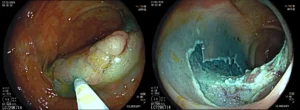

Πολύποδας παχέος εντέρου

![]()